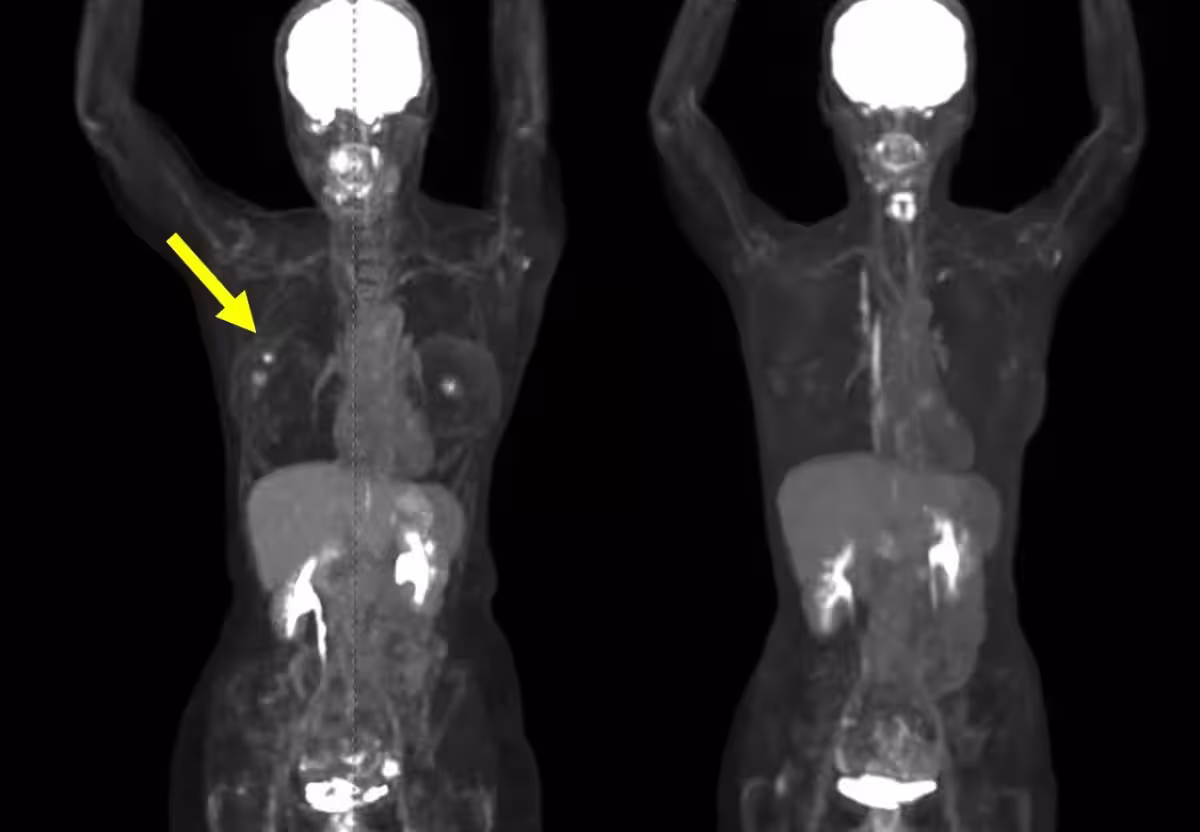

• - 再発乳がんのケース(治療4例目): 治療前の腫瘍は約37mmでしたが、3ヶ月後の評価で腫瘍が消失しました。腫瘍マーカーも著しく低下。

• - 初発乳がんのケース(治療10例目): FDG-PETでの集積が減少し、治療1ヶ月後には触診上腫瘍が確認できなくなり、その後の検査でも腫瘍が見られない状態が続きました。この成果により、完全奏功(CR)が達成されています。